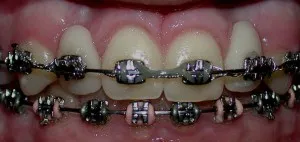

Antes y después de dos implantes de incisivos